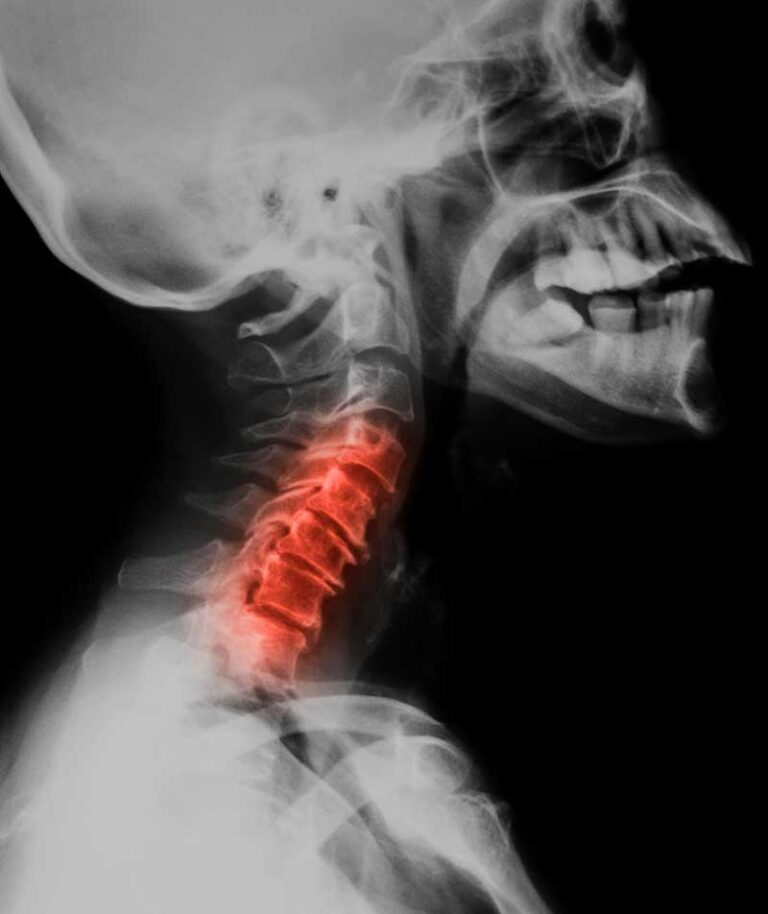

فتق دیسک گردن وقتی رخ میدهد که آسیب یا جابجایی دیسکهای موجود در ناحیه گردن فشار و تحریکی بر ریشههای عصبی یا نخاع ایجاد کنند. این وضعیت ممکن است باعث درد شدید و محدودیت در حرکت شود و حتی فعالیتهای روزمره را برای فرد دشوار کند. شدت این مشکل...

تنگی کانال گردن عبارت است از باریک شدن کانال نخاعی و یا مسیرهای ریشه عصب نخاعی در گردن. هنگامی که این باریک شدن رخ میدهد، نخاع و یا اعصاب میفشرده شوند و علائمی مانند درد، بی حسی، گزگز و ضعف در گردن، شانهها و اندامها ایجاد میکنند. اگر تنگی...